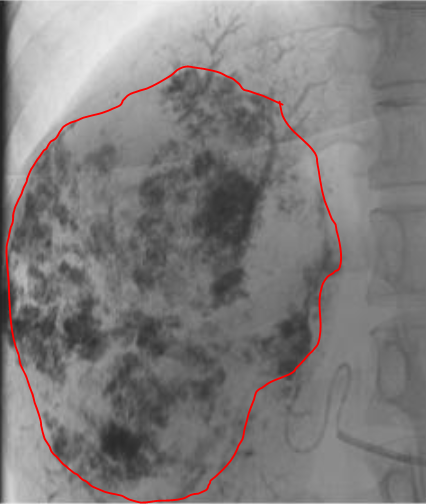

Embolisation For Liver Hemangiomas

Through a small prick in a thigh or arm blood vessels , catheters are tracked into the blood vessels feeding the hemangioma.

Treatment is administered into the haemangioma directly.

The tumor then shrinks over time , will complete resolution of symptoms.

One year follow up below , 90 % shrinked , the rest will shrink with time , and we lose nothing giving it time to completely shrink , all symptoms (pain in this case) resolved after treatment (embolisation ).